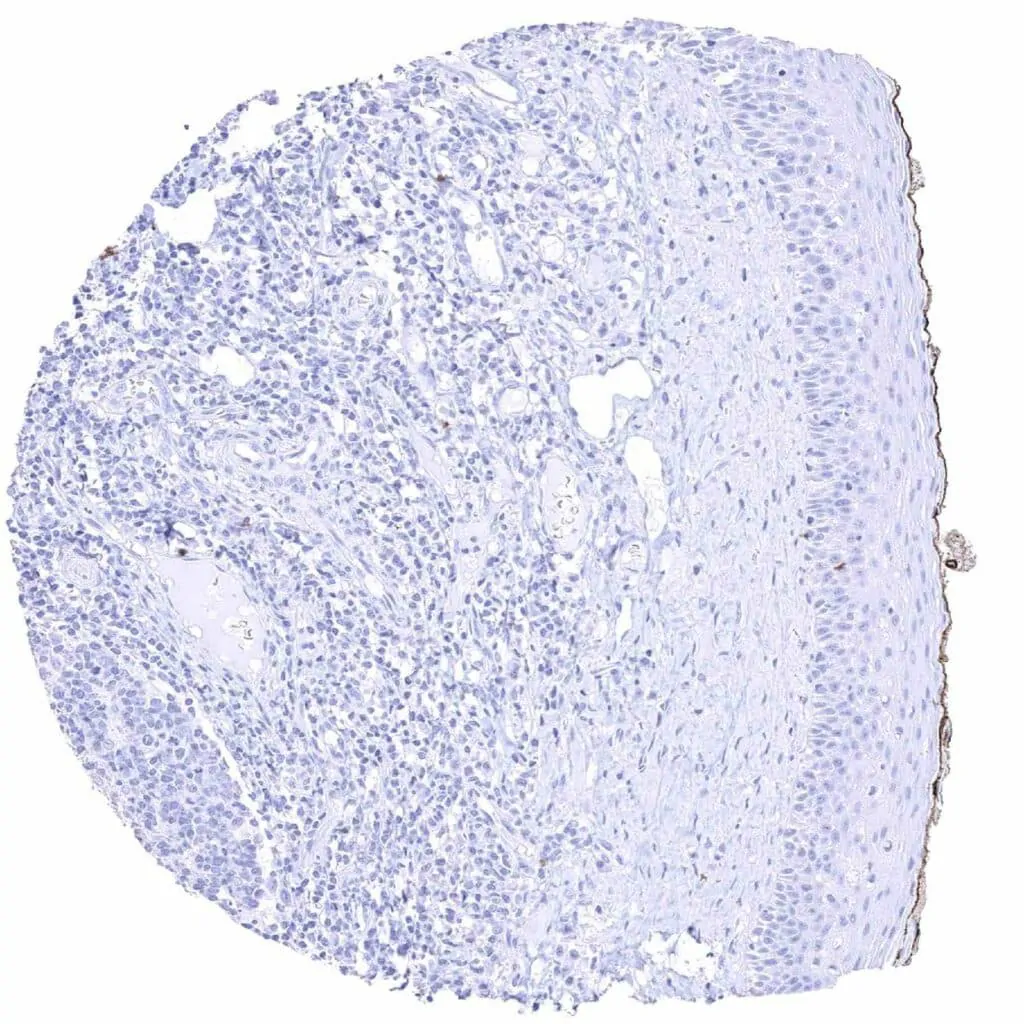

Spleen